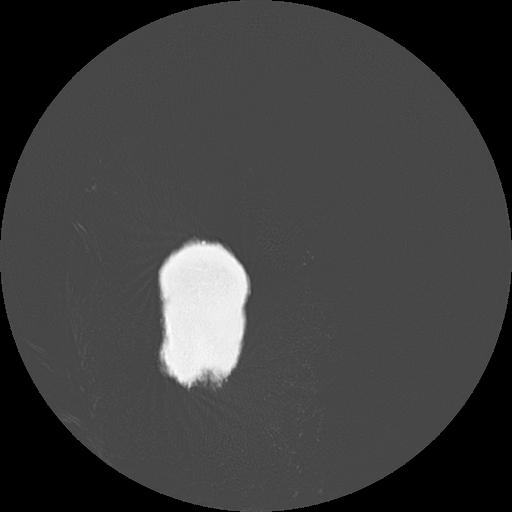

7 HUESO,,Vol,0.5,HUESO,,